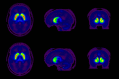

Considerable prior work suggests basal ganglia dysfunction in Tourette syndrome (TS). Analysis of a small number of postmortem specimens suggests deficits of some striatal interneuron populations, including striatal cholinergic interneurons. To assess the integrity of striatal cholinergic interneurons in TS, we used [18F]FEOBV positron emission tomography (PET) to quantify striatal vesicular acetylcholine transporter (VAChT) expression, a measure of cholinergic terminal density, in human TS and control subjects. We found no evidence of striatal cholinergic deficits. Discrepant imaging and postmortem analysis results may reflect agonal or postmortem changes, medication effects, or significant disease heterogeneity.